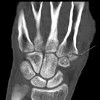

КТ кисти

Процедура назначается при переломах рук различной этиологии, включая старческий и остеопороз, при тяжелых тяжелых травмах, связанных с повреждением окружающих тканей. Манипуляции также используются для контроля состояния фрагментов после операции или сокращения и для оценки развивающегося каллуса во время лечения. КТ кисти необходима в случаях подозрения на новообразование кости и хряща верхней конечности для уточнения местоположения патологического очага, его распространенности и вовлечения окружающих тканей. Процедура рекомендуется для выявления вывихов, повреждения кистей, аномального развития структур кости или хряща, диагностики артрита, остеоартрита, подагры и остеопороза. КТ показана при подготовке к операции, чтобы контролировать динамику заболевания, уточнить результаты рентгенологического и других исследований.